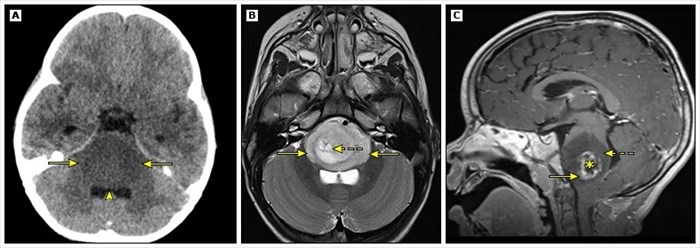

Neuroimaging of Diffuse Intrinsic Pontine Glioma